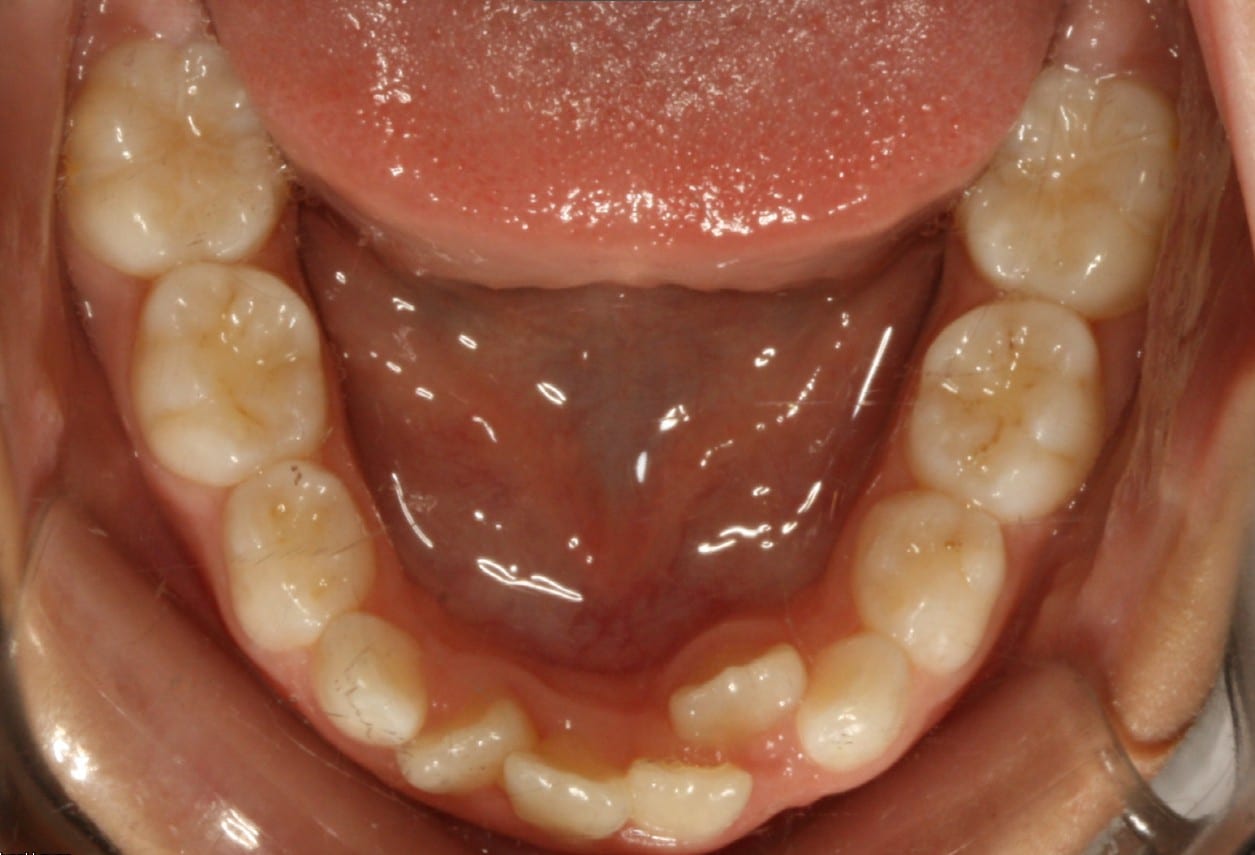

Phase I treatment with an Expander and Invisalign aligners